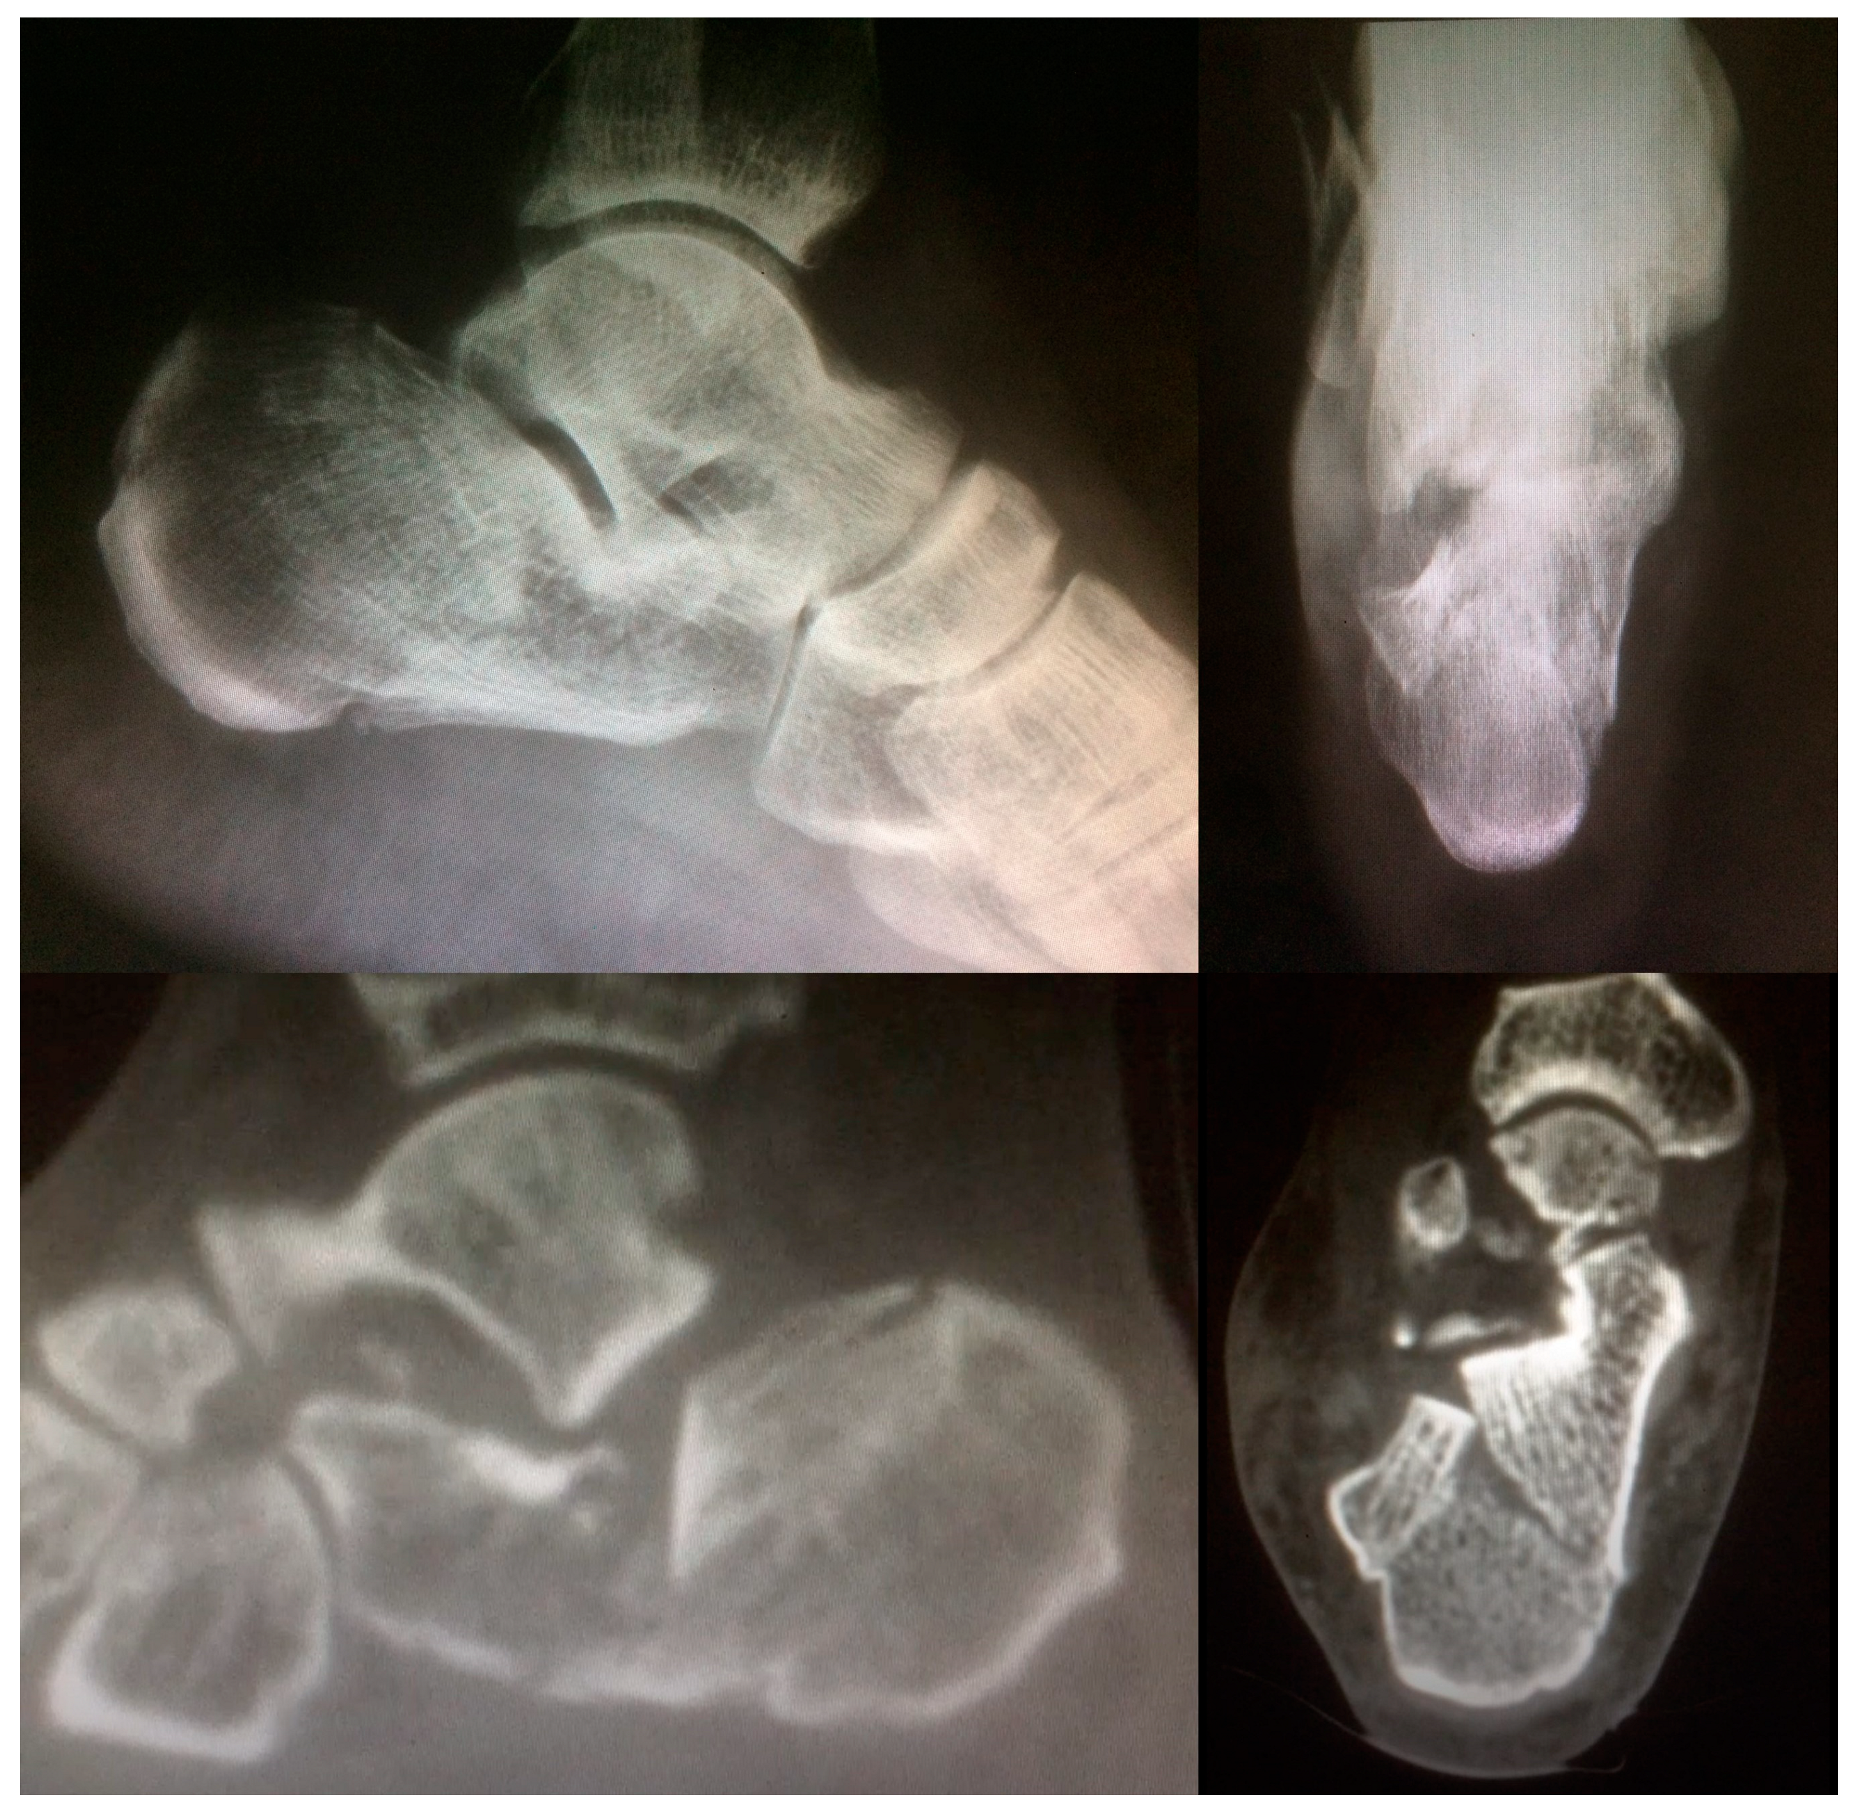

- Janzen, D.L.; Connell, D.G.; Munk, P.L.; Buckley, R.E.; Meek, R.N.; Schechter, M.T. Intraarticular fractures of the calcaneus: Value of CT findings in determining prognosis. AJR Am. J. Roentgenol. 1992, 158, 1271–1274. [Google Scholar] [CrossRef]

| Sanders Type | Patterns of fracture | ||

|---|---|---|---|

| Type I | Not displaced or minimally displaced | ||

| Type II A | A—Lateral third | ||

| Type II | Two-part fracture | Type II B | B—Central third |

| Type II C | C—Medial Third | ||

| Type II AB | AB—Involvement of the lateral and central aspects of the posterior facet of the calcaneus | ||

| Type III | Three-part fracture | Type II BC | BC—Involvement of the central and medial aspects of the posterior facet of the calcaneus |

| Type II AC | AC—Involvement of the lateral and medial aspects of the posterior facet of the calcaneus. | ||

| Type IV | Four or more fragments |